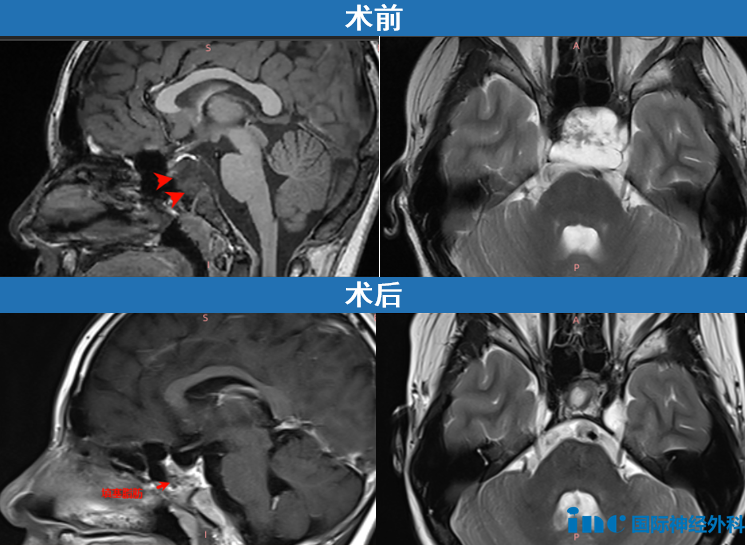

12岁男性患儿小海,影像学检查发现颅底斜坡区存在33×26×33mm巨大...